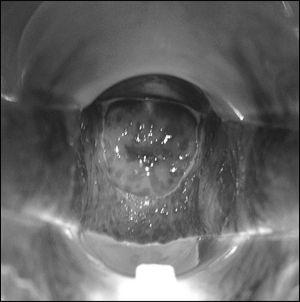

Кольпіт: фото

Зазвичай досвідченому гінеколога не складає труднощів діагностувати кольпіт. Огляд пацієнтки на кріслі проводиться за допомогою стандартних гінекологічних дзеркал. Гостре протягом кольпита візуально помітно завжди: слизова оболонка піхви має яскравий нехарактерний для здорового відтінок. Складки піхви досить пухкі, товсті, присутні набряки. Нерідко відзначаються серозні або гнійні нальоти. Якщо лікар спробує зішкребти наліт, то цілісність тканини легко пошкодиться і почне кровоточити. Особливо важкі, запущені випадки кольпіту при візуальному огляді виявляються ерозірованіем епітелію.